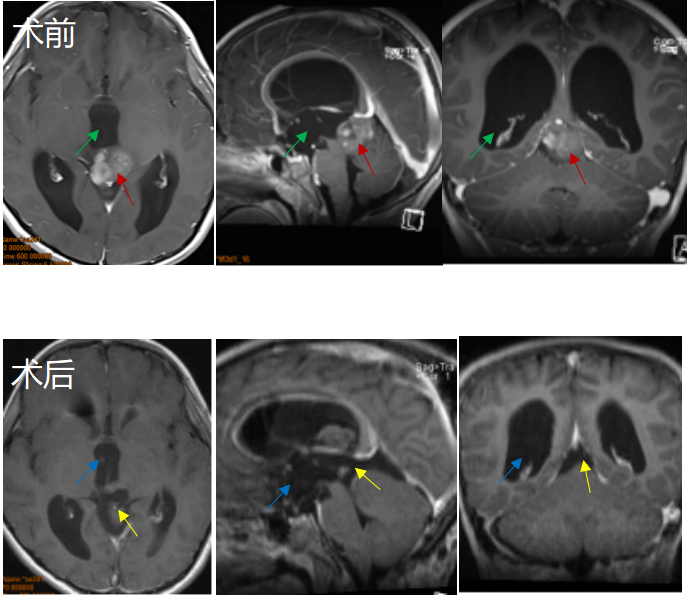

8岁男孩因头痛、眼球运动障碍等症状,检查结果为“松果体区占位合并幕上梗阻性脑积水”,一家人问遍了国内各地专家,得到的答复多是建议做脑脊液分流加辅助放化疗。事实证明,这些手段对控制小A的病情发展作用并不大。

后远程咨询INC巴特朗菲教授,教授表示有手术指征,可以全切。于是带其前往教授所在的德国INI国际神经学研究中心进行手术,手术过程中,患者俯卧位,后正中头皮切口,取幕下枕下乙状窦旁小脑上入路结合幕上经小脑幕入路,较终肿瘤得以全切除,且尽力减少了组织的损伤,对预防后期肿瘤的复发起到了较大作用。

术后一天小A依然保持清醒状态,在术后ICU观察两天之后情况良好,无明显并发症且顺利出院。目前,小A之前的各种症状全都消失,恢复了正常机体功能,较近复查时肿瘤也并无增长。